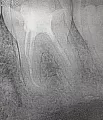

Отвалилась старая пломба, которую ставили девять лет назад. Пришел к стоматологу, она осмотрев сказала, что надо зачистить и заново запломбировать. Начав процедуру чистки, она попробовала пошатать зуб, потом сказала, что нужно сделать снимок. Снимок сделали, ее вердикт — надо удалять зуб, поскольку пошло воспаление вокруг корней, если его лечить со штифтами или еще как, через некоторое время он снова даст о себе знать и все равно придется удалить.